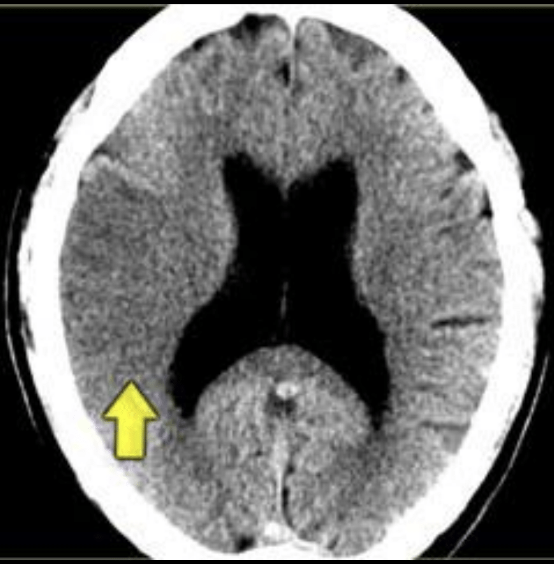

¿Qué fase es? ¿Porqué?

Fase crónica

Se observa encefalomalacia